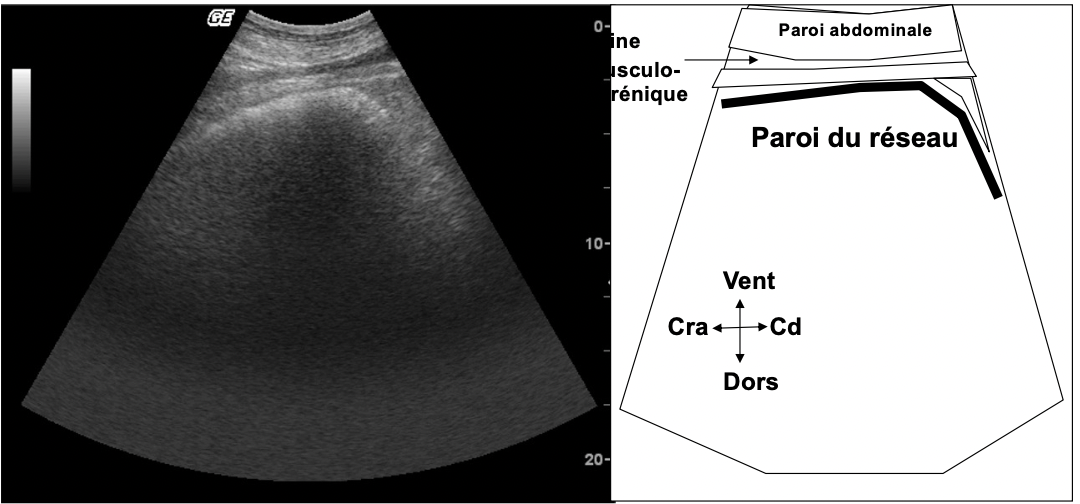

Nommer le repère anatomique à viser lors de l’écho du réseau.

Veine musculophrénique (longe la paroi du réseau)